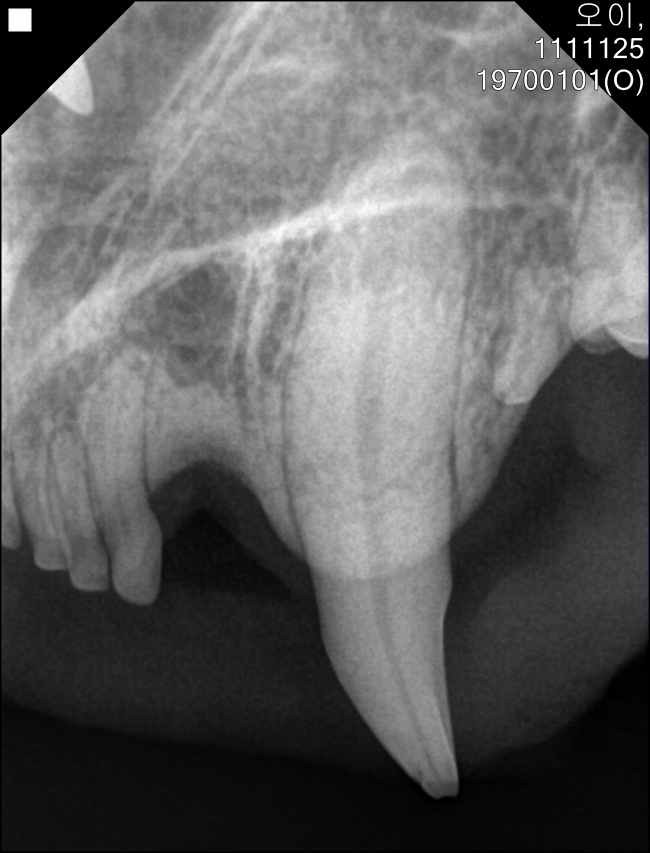

치료중 대상묘

위는 수술전, 아래는 수술중 사진